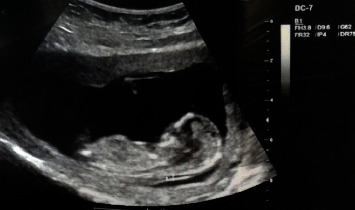

Methods: A 17-week-old female neonate with a history of prenatal diagnosis of congenital heart anomaly was admitted to Ayatollah Mousavi Hospital in Zanjan, Iran. For the diagnosis of thoracic ectopia, cordis fetal echocardiography and ultrasonography were performed. Moreover, the noninvasive prenatal testing (NIPT) genetic test performed in the 10th week of pregnancy was evaluated.

Results: The neonate was diagnosed with thoracic ectopia cordis, with the heart located outside the thoracic cavity and covered by a thin membrane. The Z scores of the analyzed maternal venous blood chromosomes were between +6 and -6, and all chromosomes had a low risk in terms of the risk of birth defects. The results of this study revealed that genetic test analysis is not enough to diagnose and predict congenital anomalies and defects. Furthermore, the findings showed that the fetus's mother continued to take folic acid after the first 3 months of pregnancy. This can be one of the risk factors involved in causing this heart defect.

Conclusion: One of the important results of this study was that the diagnostic findings of ultrasound were normal, but the findings of echocardiography were reported as abnormal. This shows that fetal echocardiography is better than ultrasound imaging in diagnosing ectopia cordis. In addition, it is recommended that pregnant women should avoid taking folic acid after the first trimester of pregnancy.